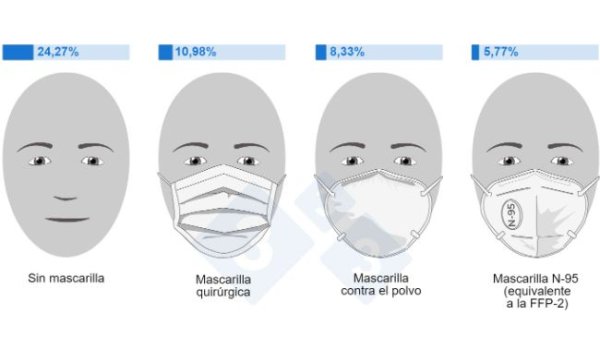

La manera más directa de disminuir la concentración de agentes infecciosos en el aire es disminuir la concentración de polvo. En este artículo se expone el uso de un sistema de ionización de partículas denominado EPI.